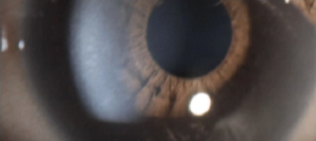

Mucopolysaccharidosis type I ocular manifestations

Corneal clouding of the eye is usually one of the first ocular manifestations in patients with the severe form of MPS I.11–13

The accumulation of GAGs and subsequent disorganization of collagen fibrils in the cornea cause corneal opacity.11,13 Corneal clouding often starts within the first year of life, causing vision impairment and often leading to blindness.12,14 Retinal degeneration and optic nerve compression can also manifest in children.12,13